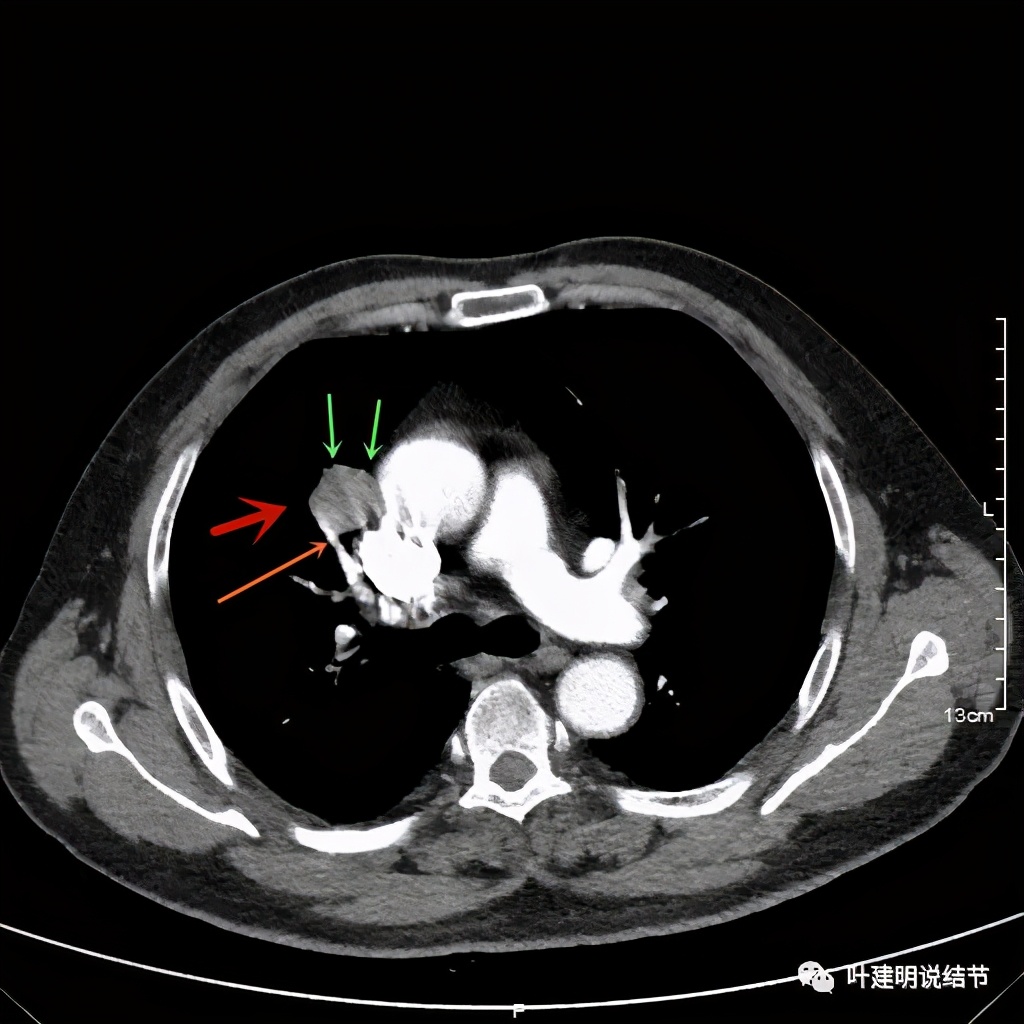

上图也示病灶密度不均,但边缘过于光滑(绿色);支气管似有截断(粉色);局部有点状钙化(蓝色)

病灶在上图层面似见支气管也是贴壁的。那么增强后又是如何呢?

上图示病灶边缘过于光滑(绿色);局部有点状钙化(蓝色)